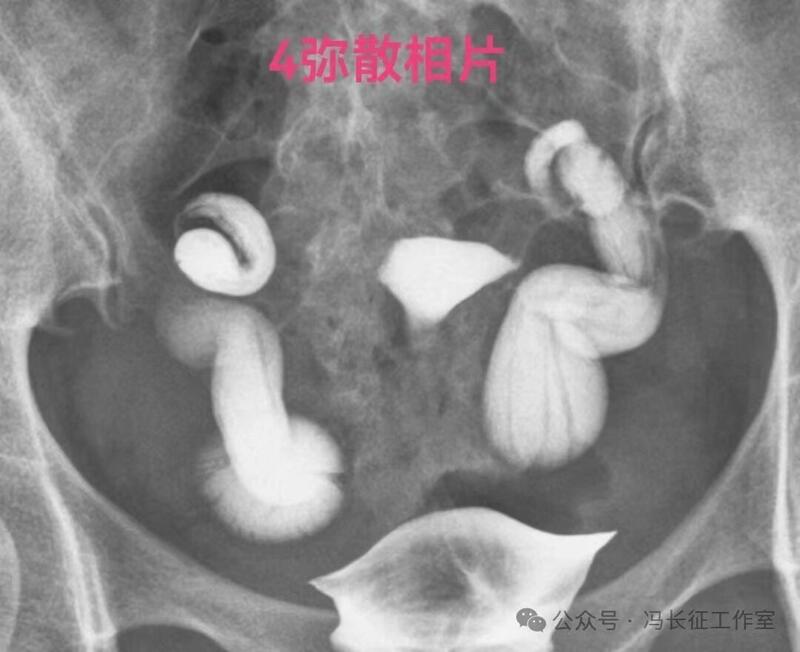

下面是一例输卵管功能良好的双侧输卵管积水的图片

双侧输卵管输卵管走行较自然柔软,近端和宫腔相通,输卵管粘膜丰富、单囊,双侧输卵管都向中间的子宫聚拢(提示输卵管系膜好),这些都提示双侧输卵管功能良好。虽然伞端没有造影剂进入盆腔弥散,输卵管管壁厚度和周围粘连情况未知;但是,从前面的信息可以初步估计输卵管功能良好。所以就给她做了腹腔镜行积水远端造口手,恢复伞部的拾卵功能,术后自然怀孕生育。